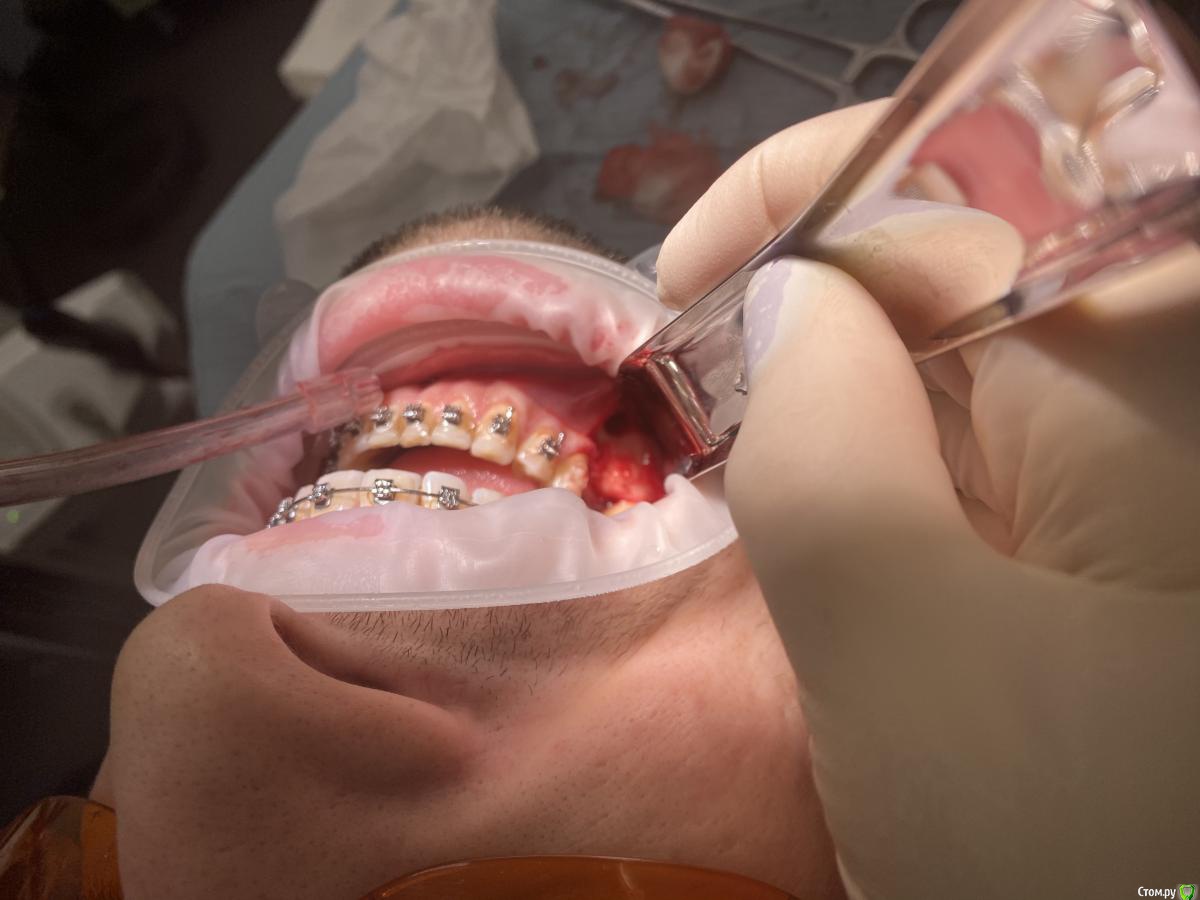

It'sGeorgy Опубликовано 7 февраля, 2020 Автор Поделиться Опубликовано 7 февраля, 2020 (изменено) Заколхозил лоскут => налепил житкотекучего на кость(стрелкой на снимке), чтобы понять там ли планирую пилить, сделал оптг => выпилил => вытащил => через месяц пластика мягких тканей + имплантат. А ментальное отверстие в 2 мм от окна отлично держало меня в тонусе на протяжении все операции. Изменено 7 февраля, 2020 пользователем It'sGeorgy 1 Ссылка на комментарий